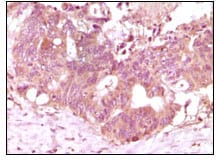

分类: 科研抗体货号: 20059别名: BFGF; FGFB; HBGF-2; FGF2应用: IHC反应种属: Human

分类: 科研抗体货号: 20073别名: HTK; MYK1; TYRO11应用: IHC反应种属: Human